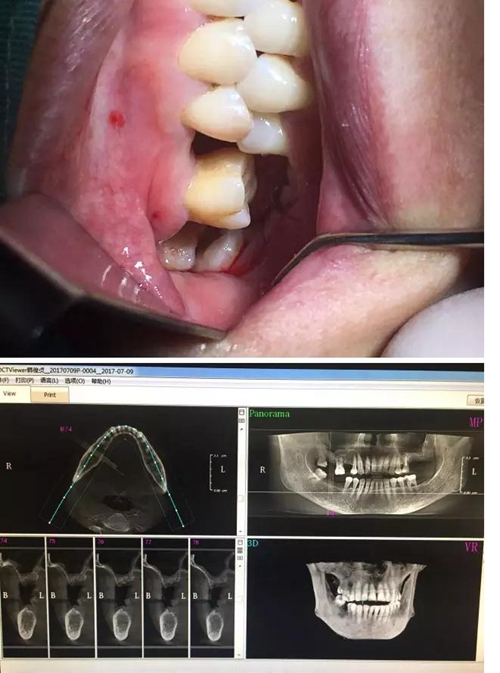

【病例分享】?jī)?nèi)提,用自體骨柱,不用骨粉

3.jpg